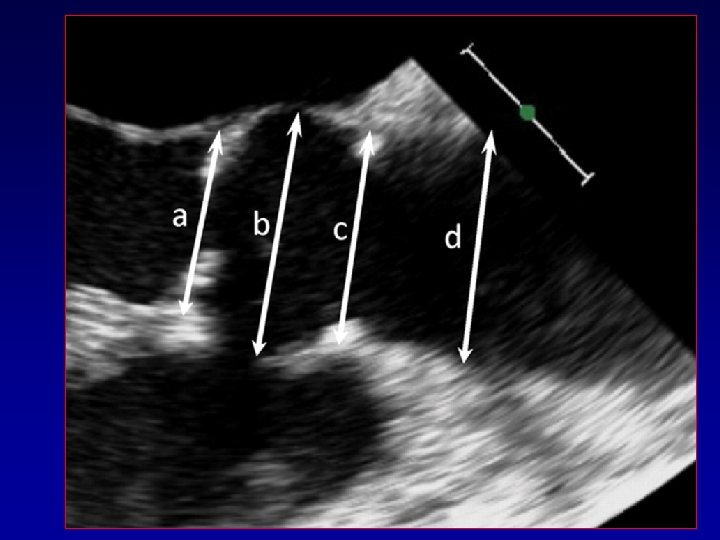

Two dimensional echocardiogram. Evangelista A Heart 2010; 96: 979 -985 Copyright © BMJ Publishing

Two dimensional echocardiogram. Evangelista A Heart 2010; 96: 979 -985 Copyright © BMJ Publishing Group Ltd & British Cardiovascular Society. All rights reserved.